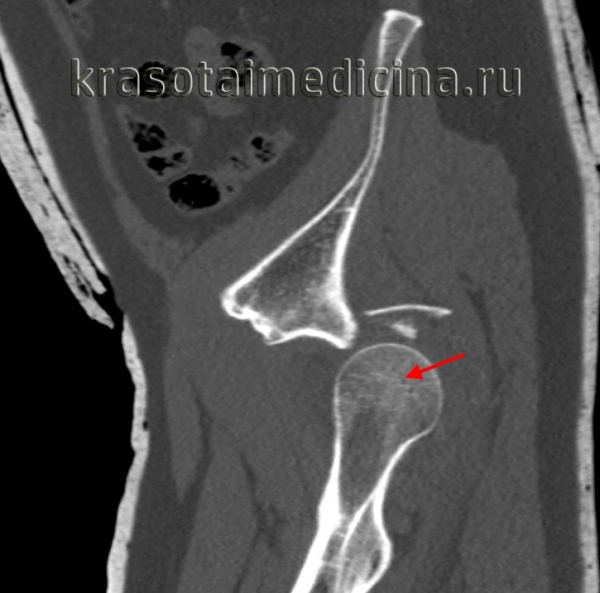

КТ таза. 3D-реконструкция. Красная стрелка – вывихнутая головка бедренной кости, синяя стрелка – «пустая» вертлужная впадина.

Рентгенография в дополнительных проекциях помогает оценить проксимальный сегмент бедренной кости с целью исключения переломов головки и шейки бедра. После вправления вывиха необходимо провести КТ, чтобы оценить результаты вправления, уточнить целостность вертлужной впадины и исключить наличие костных фрагментов в полости сустава. Вывихи изредка сопровождаются переломами головки бедра, которые должны быть соответствующим образом выявлены и устранены.